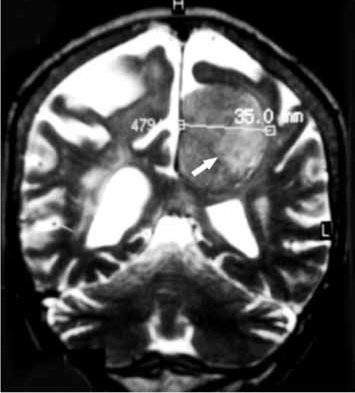

Paciente com 60 anos de idade se apresenta com quadro de cefaleia moderada há 3 meses, e há 15 dias discreta redução da atenção, moderada hemiparesia direita e vertigens. Não tem antecedentes mórbidos; o exame clínico é normal e o exame neurológico confirma os achados. A ressonância magnética é apresentada a seguir.

Com esses elementos, qual a sua primeira impressão diagnóstica?